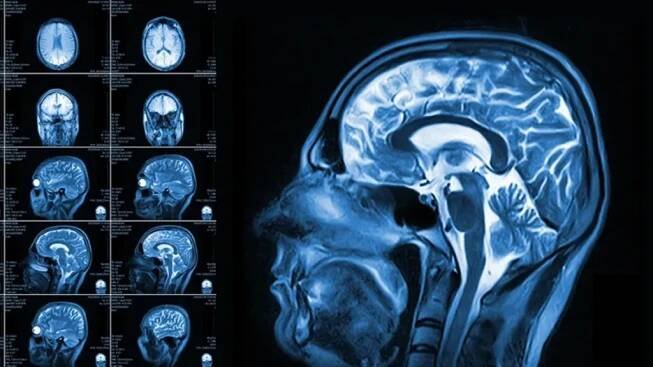

CT je označení pro speciální rentgenové vyšetření – výpočetní tomografii (anglicky computed tomography, často používaný termín počítačová tomografie není správný). Tomografie znamená vyšetření ve vrstvách.

13. 6. 2023Počítačová tomografie neboli CT používá rentgenovou technologii k zobrazení různých částí lidského těla včetně kostí, svalů, vnitřních orgánů a krevních cév.

Počítačová tomografie (CT) je pokročilá zobrazovací metoda, která umožňuje vytvořit detailní snímky vnitřních struktur těla. Počítačová tomografie je široce využívána pro diagnostiku a monitorování různých stavů.

CT je vyšetřovací metoda využívající rentgenového záření k zobrazení vnitřku lidského těla. Na rozdíl od běžného rentgenové snímku vytváří CT soustavu mnoha „řezů“ vyšetřovanou oblastí lidského těla.

Výpočetní tomografie (CT) je pokročilá zobrazovací metoda, která umožňuje detailní pohled do vnitřních struktur lidského těla.